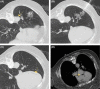

Air embolism should be treated promptly with high fraction of supplemental oxygen and repositioning to help facilitate reabsorption of the air bubble. Hyperbaric oxygen therapy should be given to those with severe disease.